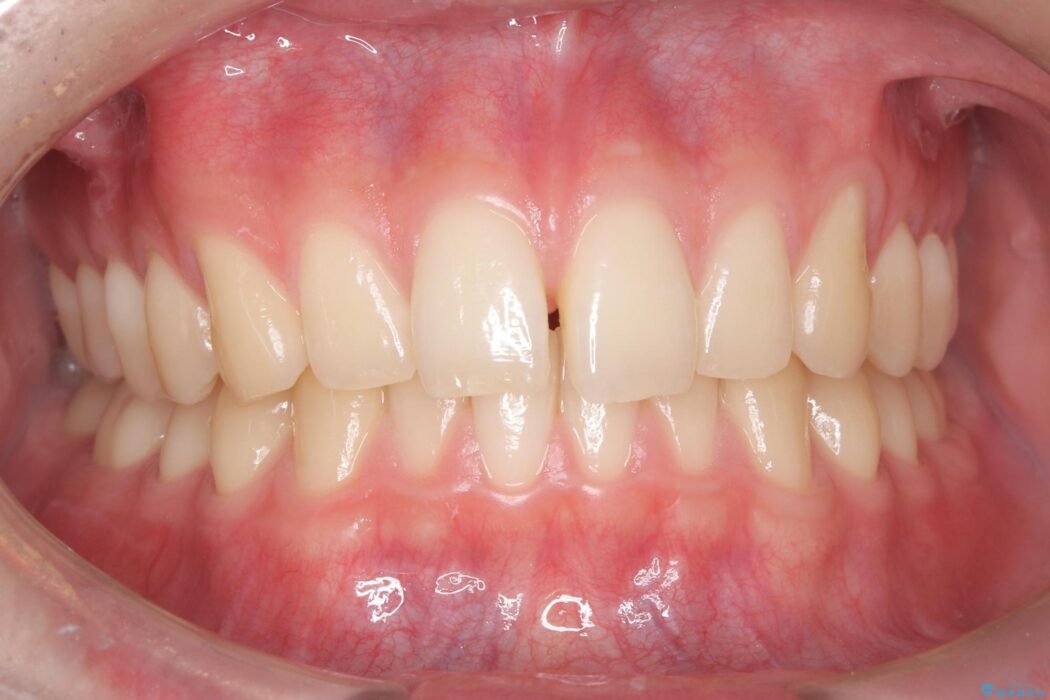

上の前歯のすきっ歯を治したいとご来院された患者様です。

上顎中切歯間の隙間の他にもフロスが抵抗なく入るスペースが上顎は数か所ありました。スペースを閉じ下顎の歯列弓との調和をとるためIPRを行いました。

下顎の舌側傾斜気味の前歯も唇側へ歯軸傾斜させています。